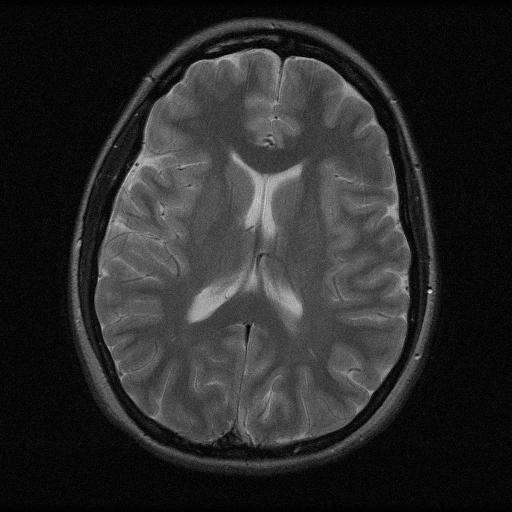

6.3. MR Image reconstruction

The second imaging application is concerned with medical imaging. Following the ideas from [32, 34], we simulate a multi-channel MRI sensing set-up, first using the same sine waves as in the previous experiment (results displayed in Fig 10), and then using spherical beam pattern (see in Fig. 11 for the results). We generate the classical Shep-Logan phantom, and set its dimension to .

The first experiment, depicted in Fig. 10 shows the results obtained by our method when using a Daubechies 4 sparsifying dictionary. Our results are compared to the single sensor analysis, and the results obtained by the Sum-of-Squares recovery [34, 32].

The recovery is obtained from noisy measurements, in which some additive Gaussian noise with variance has been added. The measurements are obtained by subsampling ( samples) of the Fourier transform. We see here that the fused compressed sensing is better capable of handling a multi-channel problem with unusual illumination (compared to the Sum-of-Squares method). Moreover, more details are preserved, when compared to the single sensor analysis method.

Some noise still appears in the image, but can easily be thresholded further if needed. One important aspect of MR Images that hasn’t been considered in this research, is the fact that they are sparse in gradient. One usually prefers to minimize the Total Variation instead of the norm or another frame using analysis.

Although we have not explicitly written the theory here, the recovered images in Fig. 11 show the results when using a TV minimization instead of the analysis.

The results were obtained from a spherical beam illuminating the input image. The measurements are obtained by sampling ( samples) of the Fourier coefficients at random iid from a Gaussian distribution. Again, some Gaussian noise with variance is added to every measurements.

As presented in these examples, our method is capable of handling highly complex signals in potentially many dimensions yet keeping a very low number of samples taken. We can also empirically verify that the presented approach enjoys more robustness to noise and variations in scene illuminations than other known methods.

This behavior is true for both images, which are real-world images of brain scans. It is worth keeping in mind that SSIM is a structural similarity which tries to emulate the human visual perception while the other metrics are pure machinery. As can be seen both from the figures and the tables, the proposed method performs at least as well as previous approaches, and may behave better when considering total variation minimization.